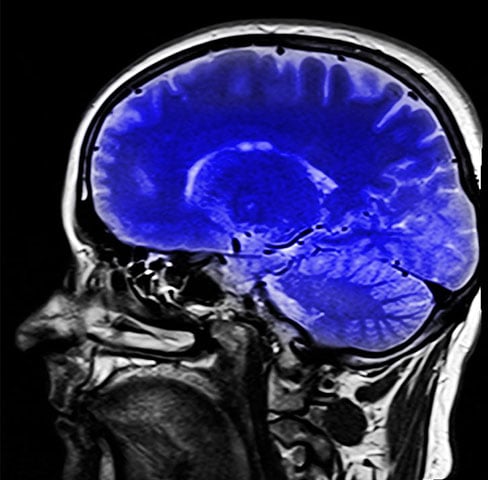

Alerta sobre remédios para dormir: pesquisa conclui que aumentam risco de demência